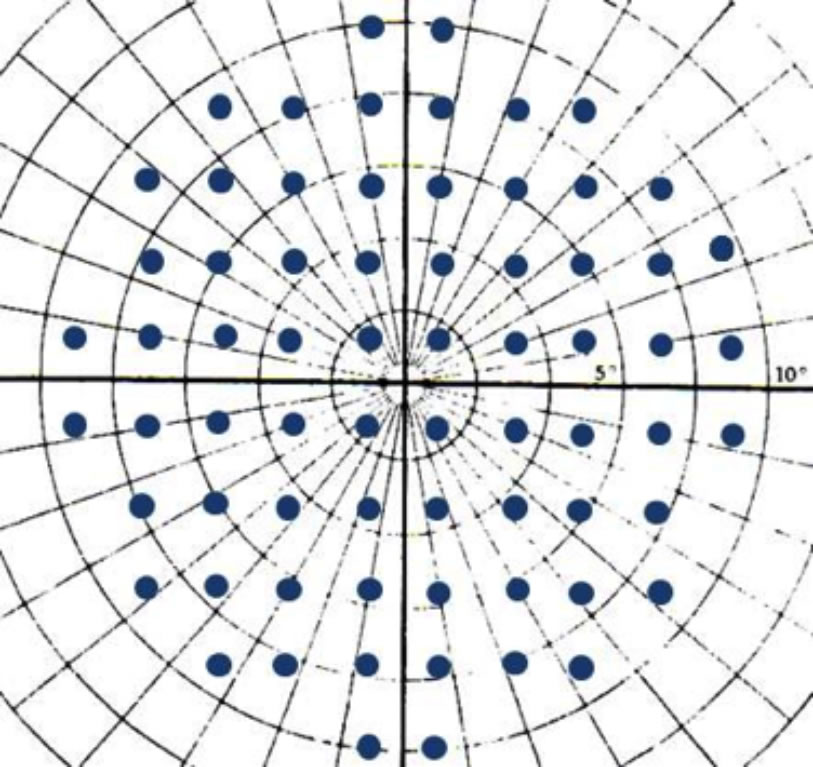

Examination strategies

Static perimeters test the differential light sensitivities of specific retinal locations distributed on a fixed grid pattern. The spacing between these locations (points) varies according to the examination area targeted. When testing the central 30 degrees and central 24 degrees with the Humphrey perimeter, the grid points are spaced 6 degrees apart. The central horizontal points may be distributed on the horizontal axis (programme 30-1 or 24-1), or at equal distances from the horizontal axis (programme 30-2 or 24-2). The advantage of using the central 30-2 or 24-2 programmes lies in the spacing of the central horizontal points at 3 degrees from the centre of the field, with greater sensitivity to changes across the horizontal retinal raphé (nasal steps) (Figure 5).

Figure 5a. The central 30-2 programme. Note the distribution of the horizontal test spots at equal distances from the horizontal axis (3 degrees). This insures more detailed exploration of horizontal defects (nasal steps). Note also the small number of test locations in the central 10 degrees. Compare this with the number and distribution of test locations in the central 10-2 programme.

Figure 5b. The central 10-2 programme. The space between test spots is 2 degrees. The horizontal test locations are distributed at 1 degree from the horizontal axis.